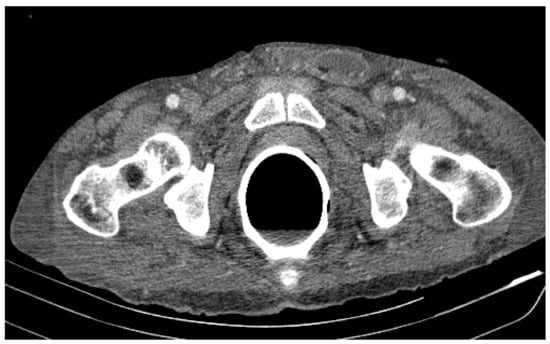

• At the rectal level, the presence of a foreign body is highlighted, with regular edges a maximum diameter of 65 mm (Figure 7 and Figure 8).

Figure 7. Patient’s computer tomography: the presence of a foreign body is highlighted.

Figure 8. Patient’s computer tomography: the presence of a foreign body is highlighted, with regular edges and a maximum diameter of 65 mm.